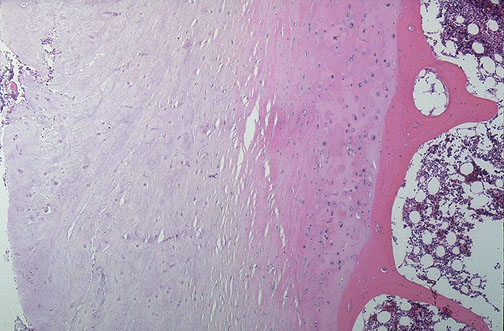

A normal intervertebral disc is shown here at medium power. The disc consists of fibrocartilage that provides flexibility to the vertebral column. A vertebra with bone and marrow is present at the right.